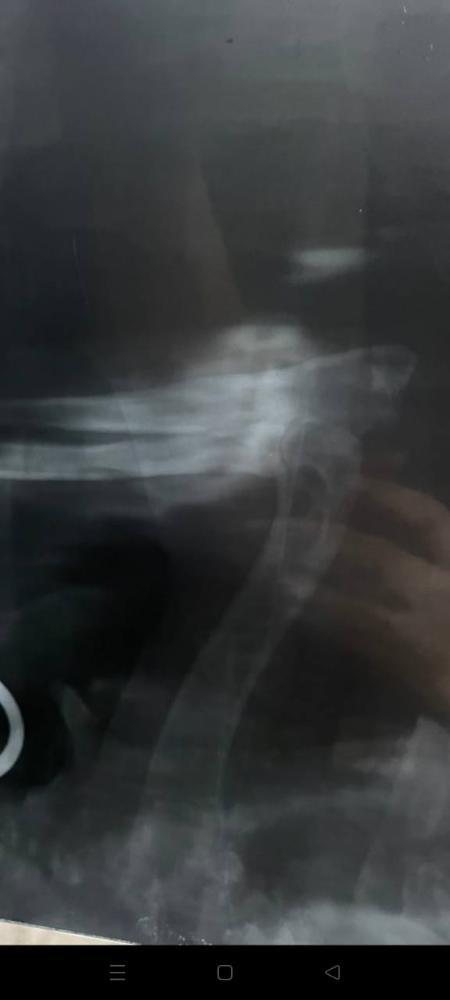

Кратко, нашли в январе 2024 , когда нашли не ходил, передняя лапа телепалась и шишка была на локте, не вставал на лапу, прокололи бонхарен, помогло. Сказали артроз.

Прикладываю старый рентген.